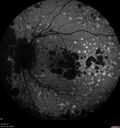

79 year old vision is in for a checkup with no visual complaints in the left eye. This is her better eye. VA 20/200 OD, 20/50 OS. 3 years ago she had a CRVO in the left eye. She is also diabetic for 20 years, has carotid insufficiency and anemia. Left eye shows CME. This was not treated and the vision improved to 20/40 over the next year although mild edema persisted.